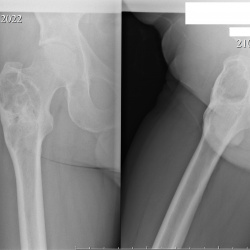

Здравствуйте коллеги. В н.3 диафиза бедренной кости вижу утолщение , вроде  ничего серьезного .Как бы вы интерпретировали? Свежей травмы не было.